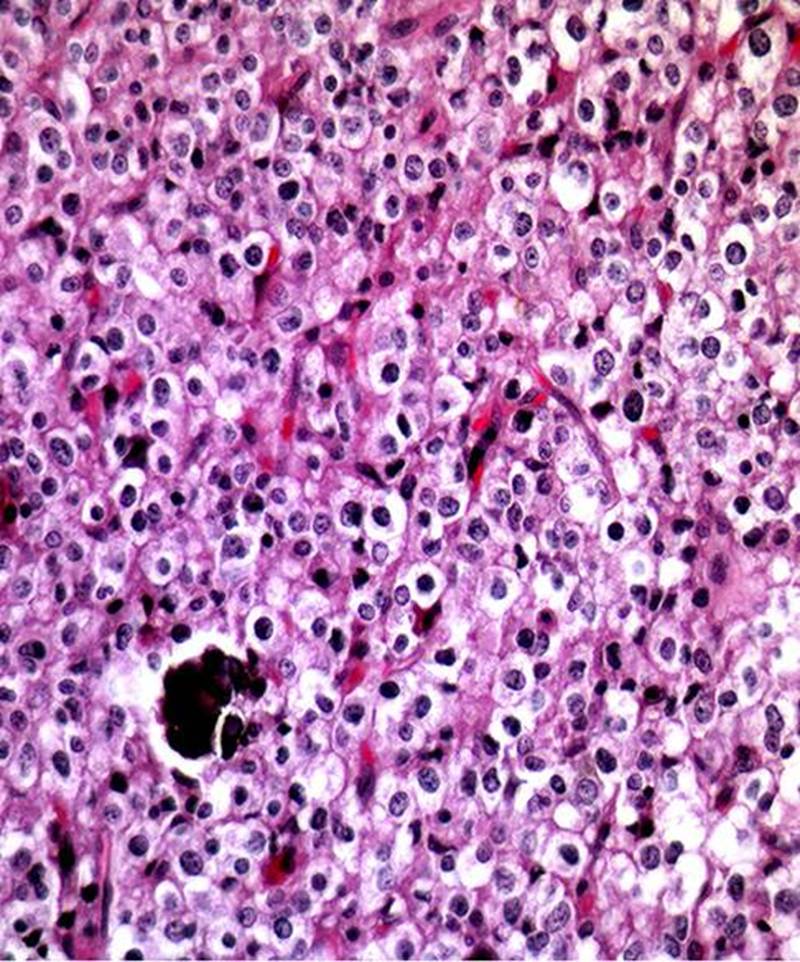

Characteristic loss of chromosomes 1p,19q

Oligodendroglioma

10-15% of all gliomas

Predilection for cortex

Gyriform calcification, higher grade lesions may enhance

Tend to like to stay in 1 of the gyri

Can have calcifications

1 gyri

Perinuclear halos or fried egg appearance

Delicate capillaries

Calcification

Chicken wire vasculature

Perineuronal satellitosis

Subpial accumulation

Delicate capillaries (chicken wire)

1p, 19q loss